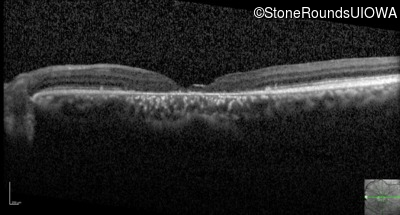

Optical Coherence Tomography - Left - 20/125 +1

Exemplar / OCT Stack

OCT Stack